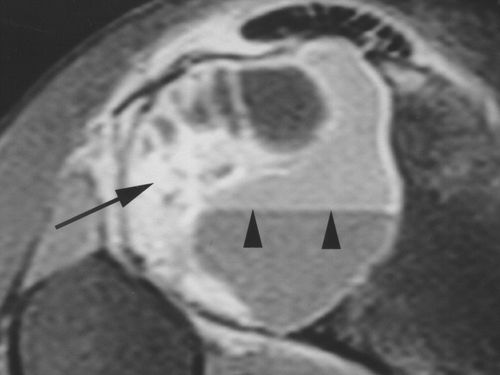

动脉瘤样骨囊肿可能在巨细胞瘤内形成[1]。如果患者的年龄和病变的影像学表现提示巨细胞瘤(图10A),并且CT,MRI或两者的发现显示除了增强的固体成分之外的液体水平,则应该怀疑这一点(图 。10B)。

图10B -25岁女性,巨细胞瘤伴继发性动脉瘤样骨囊肿形成。脂肪饱和度的T1加权图像可以看到,病变内的增强固体成分(箭头)和液体 – 液体水平(箭头)。